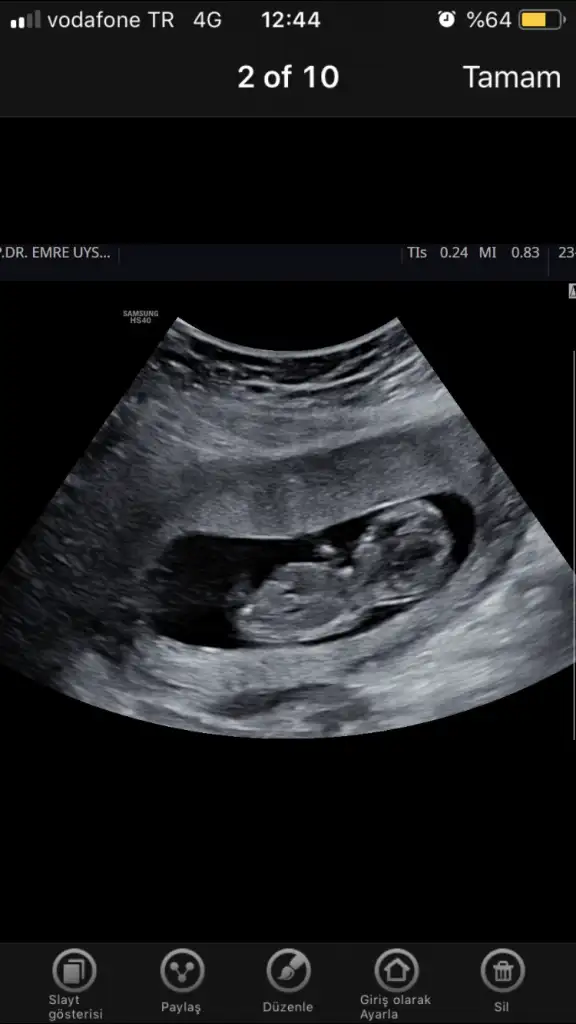

dr soylemeden siz gorun genital nub teorisi ( bebegin cinsiyeti)

Erkek erkek.önceki usg de bu kadar belli değildi nub.tabi doktor daha iyi bilir hayırlısı olsun